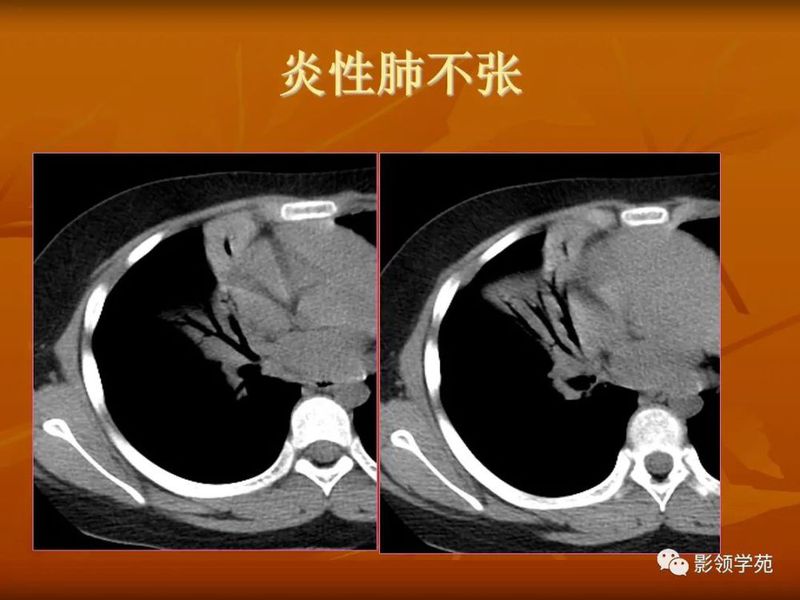

熟悉掌握肺部基本病变的CT表现,是诊断肺部疾病的基础,要仔细观察CT片上所呈现的各种表现,发现其特点,并对这种CT特点与病理表现的相互联系有清楚的理解,以便准确解释CT检查所包含全部信息和细微差别,要特别注意是相同疾病,不同表现,不同疾病,相同表现,要求我们必须密切结合临床症状及各种实验室检查指标,对每一个CT特征进行仔细的分析与鉴别,做出较为准确的诊断结果。